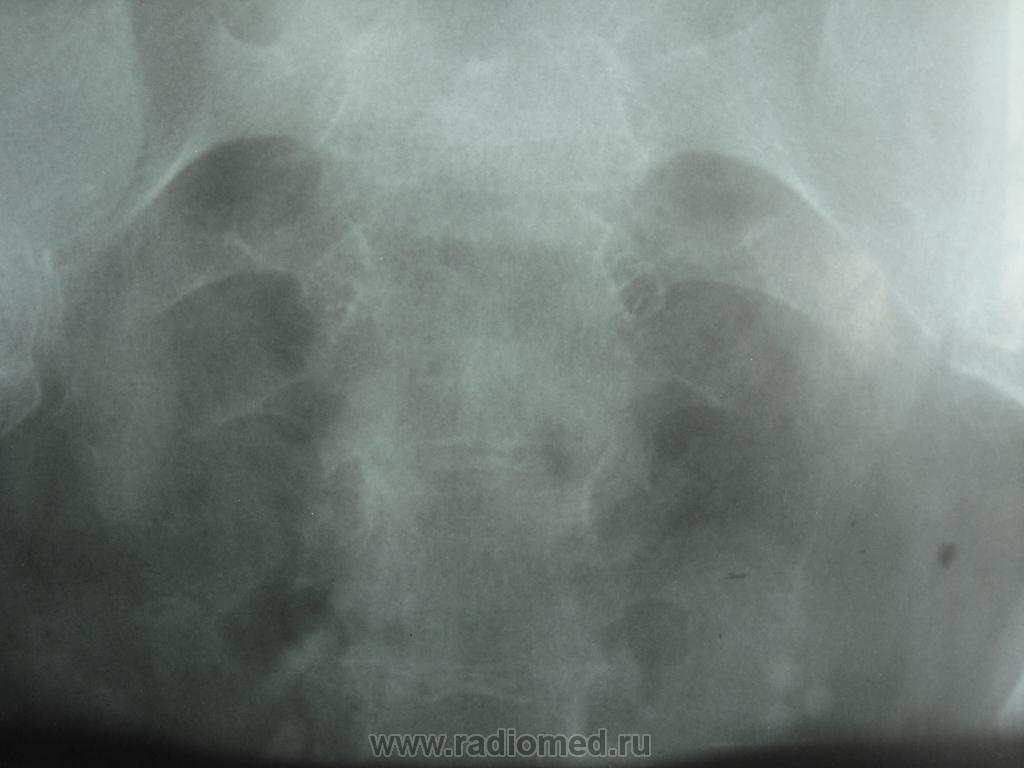

Удвоение слева, думается на рено-вазальный конфликт верхней лоханки слева (без доказательств, хочется еще отсроченного снимка). Дивертикул мочевого пузыря с камнем или камнями, в который впадает левый мочеточник. Не настаиваю

На самом деле просто полное удвоение почки, с гидронефрозом краниальной ЧЛС, а это всего навсего расширенный мочеточник так смотрится, все проблема на уровне устья.

вообщем то ничего особенного, просто уретероцеле слева у уролога вызвало восторг, вот я и решила его на сайт выставить. на днях прооперировали, камушки убрали.

Удваение ЧЛС ,и мочеточника слева.с признаками затрудненного оттока на уровне устья.Уретероцеле с наличием камня слева.